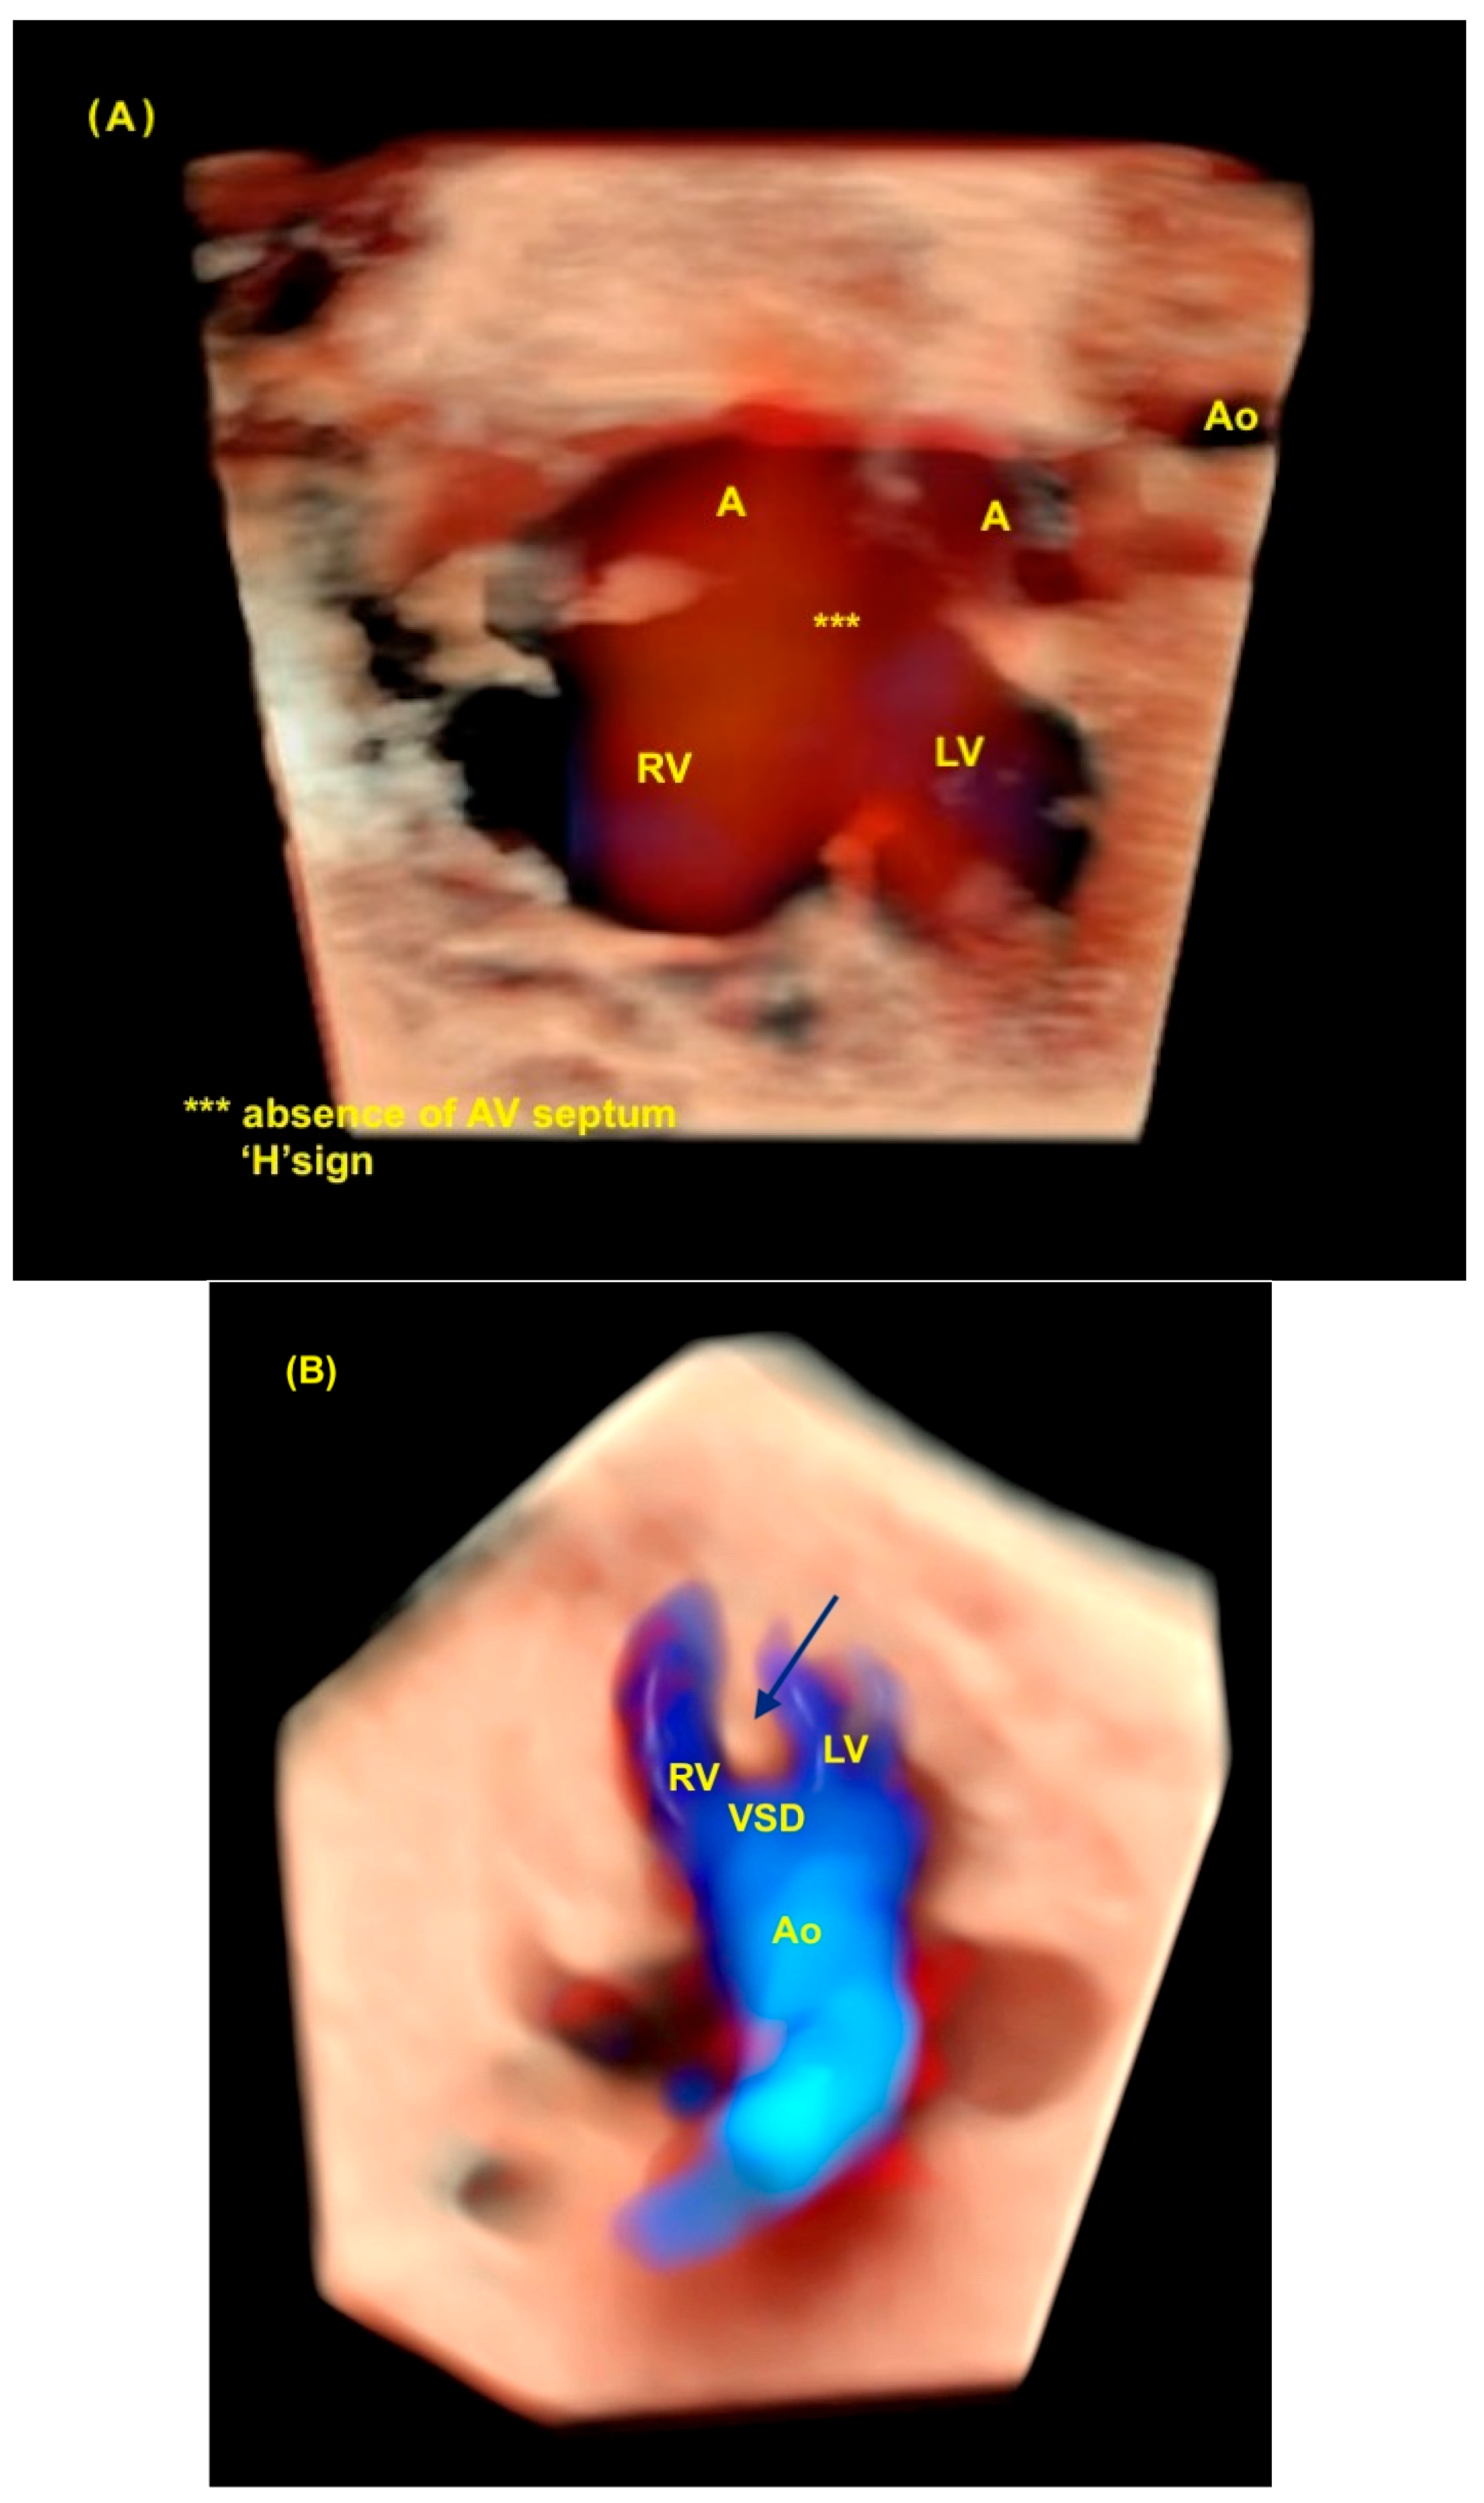

7. Isomerism

8. Atrioventricular Septal Defect

9. Tetralogy of Fallot